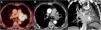

A 70-year-old ex-smoker man (45 pack-year history of smoking; quit smoking 4 years earlier) presented to our hospital with a new-onset symptomatic AF. His past medical history was significant for coronary artery disease (treated with CABG four years earlier), mitral valve disease (treated with mitral valve replacement at the same time of the CABG), hyperlipidemia, and chronic obstructive pulmonary disease. Since the AF episodes became persistent in spite of medical treatment, a cavotricuspid isthmus (CTI) ablation was planned. The CTI ablation procedure was successful for controlling the patient's AF. A chest radiograph performed at that time showed a subtle left parahilar opacity that was presumed to be of infectious origin (Fig. 1); however, given the absence of thoracic symptoms, a thoracic computed tomography (CT) was recommended. A chest CT was performed 2 weeks later and showed a left hilar mass invading the mediastinum and the left internal mammary artery (LIMA) graft to the left anterior descending coronary artery, consistent with a lung cancer (Fig. 1). The patient denied any chest pain, hemoptysis or coughing in the previous weeks, and an electrocardiogram (ECG) performed at that time (post-CTI) did not show any abnormalities. A bronchoscopic biopsy confirmed a large cell undifferentiated lung carcinoma. A contrast-enhanced whole-body positron emission tomography (PET)/CT detected small liver and adrenal metastases, consistent with a stage IV lung cancer. The patient was started on systemic chemotherapy, but unfortunately the cancer did not respond to treatment. A follow-up PET/CT performed 3 months later showed an increase in the size of the lung mass, a decrease in the diameter of the LIMA graft secondary to an encasement by the surrounding tumor (Fig. 2). Shortly after this follow-up study, the patient presented to the Emergency Department with tachycardia, chest pain, a new ST elevation on ECG in the precordial and lateral leads, and elevation of cardiac troponin levels, consistent with an extensive myocardial infarction. The patient was admitted to the oncology unit and died from cardiac arrest 24h later.